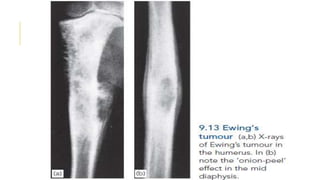

EWING’S SARCOMA

Ewing’s sarcoma is believed to arise from endothelial cells

in the bone marrow.

It occurs most commonly between the ages of 10 and 20

years.

Occure usually in a tubular bone and especially in the

tibia, fibula or clavicle.

The patient presents with pain – often throbbing in

character – and swelling. generalized illness and pyrexia.

X-ray usually shows an area of bone destruction which is

predominantly in the mid diaphysis. New bone formation

may extend along the shaft and sometimes it appears as

fusiform layers of bone around the lesion – the so-called